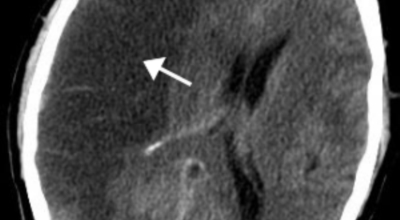

전 세계적으로 2초에 한명씩 발생하고, 6초에 한 명씩 사망하는 질병으로 국내에서도 3대 사망 까닭 중 하는 뇌졸중. 뇌졸중은 뇌 일부분에 혈액을 제공하는 혈관이 막히거나 터지면서 발생하는 병으로 고혈압이 뇌졸중의 대표적인 이유가 되는 것 질환입니다. 뇌졸중은 뇌혈관이 막히거나 터져서 뇌세포가 훼손되서 생기는 신경학적 증상입니다.

뇌졸중은 뇌경색과 뇌출혈 두가지로 나뉘게 돼요. 먼저 뇌경색은 뇌혈관이 막혀 영양분과 산소를 제공하는 피가 통하지 않는 상태로 원은은 크게 세 가지로 나눌 수 있는데요 동맥경화증이 생겨 좁아진 부위로 인하여 혈액공급이 부족해지거나 좁아지다가 결국 막혀버리는 경우, 큰 혈관에서 분지한 작은 혈관들이 고혈압 등으로 압박을 받으면 혈관이 막히는 경우가 있어요.

또한 심장 판막질환이나 심방세동 또는 심근병 등과 같은 심장 질환이 있는 경우 심장에서 혈전이 만들어지고 그게 뇌로 흘러가게 되면 뇌혈관을 막게 되는 경우가 있어요. 뇌출혈은 뇌경색과 반대로 뇌혈관이 터져서 생기는 뇌내 출혈과 거미막하 출혈로 나누게 돼요. 거미막하출혈은 혈관벽의 약한 부분이 부풀어 오르는 뇌동맥류가 터지는 경우와 관련성이 크다고 해요.